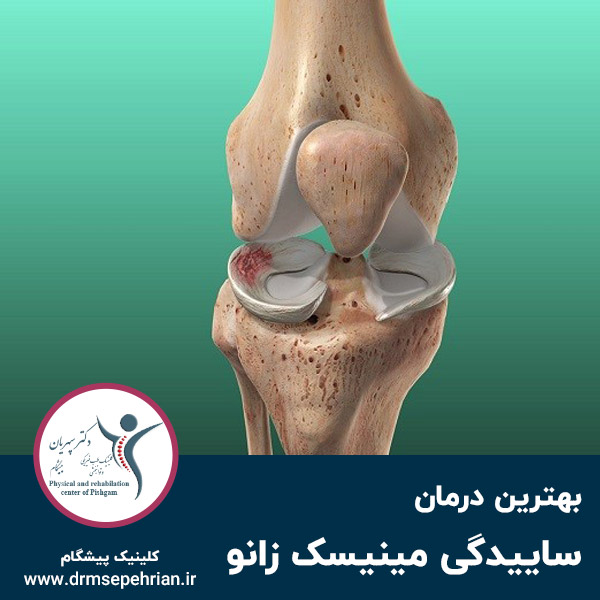

ساییدگی مینیسک زانو وضعیتی است که اگر درمان نشود ممکن است منجر به پارگی مینیسک شود. بر اثر عواملی چون حرکت مداوم و چرخش ناگهانی زانو، مینیسکها بر روی هم میلغزد و این مشکل ایجاد میشود؛ که طی آن غضروفهای هلالی استخوان ران و ساق پا دچار ساییدگی میشود.

این وضعیت درد زانو را به همراه دارد و انجام حرکت زانو را برای شما با دشواری همراه میسازد. به همین دلیل باید هرچه سریعتر نسبت به تشخیص آن اقدام نمایید تا روند درمان خود را آغاز کنید. در ادامه این مقاله طب بوک دکتر سپهریان به طور کامل در خصوص ساییدگی مینیسک زانو و راهکارهای درمانی آن توضیح میدهند؛ پس همراه ما باشید.

ساییدگی مینیسک زانو چیست؟

ساییدگی مینیسک زانو یکی از مشکلات ارتوپدی است که در آن غضروفهای هلالی استخوان ران و ساق پا دچار ساییدگی میشود. این مشکل بر اثر حرکات تکراری و مداوم زانو و چرخش ناگهانی زانوها به وجود میآید که میتواند غضروفهای زانو را به سمت نابودی ببرد. ساییدگی مینیسک اگر درمان نشود ممکن است منجر به پارگی این عضو مهم شود؛ در نتیجه امکان حرکت زانو به طور کامل از بین میرود.

در این حالت مجوعهای از علائم و نشانهها برای افراد ایجاد میشود که نشان از فرسایش تدریجی مینیسک و آسیب به مفصل زانو دارد. ازشایعترین علائم ساییدگی مینسک میتوان به درد و سفتی در مفاصل زانو اشاره کرد که حرکت زانو را با سختی مواجه میکند. در ابتدای امر علائم این مشکل کمتر است؛ اما هر چه که از زمان ابتلا به این بیماری میگذرد، علائم آن نیز بیشتر میشود. بنابراین بهتر است که هرچه سریعتر نسبت به اتخاذ یک درمان مناسب اقدام کنید تا مینیسک زانوی شما به طور کامل از بین نرود.

ساییدگی مینیسک زانو یک بیماری ارتوپدی است که بر اثرحرکت مداوم و چرخش ناگهانی در زانو ایجاد میشود. در این شرایط علائمی چون درد و ناراحتی برای افراد ایجاد میکند که حرکت زانو را برای شما دشوار میسازد. بسیار مهم است که هر چه سریعتر برای آغاز روند درمان به بهترین پزشک متخصص طب فیزیکی مراجعه کنید. پزشک با تجویز راهکار موثر از جمله پی آر پی میتواند در سریعترین زمان ممکن نسبت به درمان این وضعیت در شما اقدام کند. بنابراین از ایجاد مشکلاتی چون پارگی مینیسک زانو جلوگیری میشود.